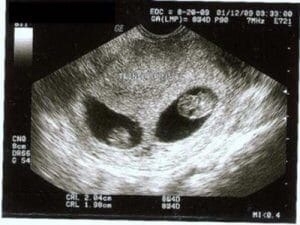

Сначала лимона вдруг захотелось, потом то в жар, то в холод...🌤️🌪️подумала, может погодка виновница этого беспредела... В голову полезли странные мысли..... Когда я увидела вот это фото, меня словно током ударило! 🤩👉🎁❤

Эти два маленьких человечка, которым уже 5 недель и я смотрю на них и улыбаюсь 😊😊😊😊😊